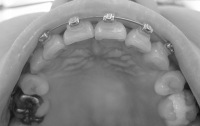

下から。

2008/4/15撮影

2008/5/20撮影

残る隙間は左側が1ミリ、右側が0.5ミリほど。